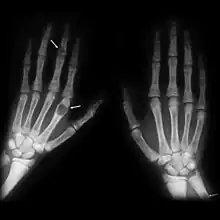

| Osteitis fibrosa cystica of the tibia. Arrows point to the brown tumors which are typically present in bones of people with OFC. | |

X-rays may also be used to diagnose the disease. Usually, these X-rays will show extremely thin bones, which are often bowed or fractured. However, such symptoms are also associated with other bone diseases, such as osteopenia or osteoporosis.[29] Generally, the first bones to show symptoms via X-ray are the fingers.[22] Furthermore, brown tumors, especially when manifested on facial bones, can be misdiagnosed as cancerous.[29] Radiographs distinctly show bone resorption and X-rays of the skull may depict an image often described as "ground glass" or "salt and pepper".[30][31] Dental X-rays may also be abnormal.[2]